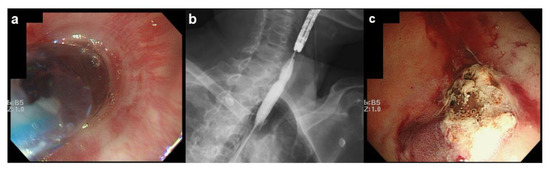

3.2. Case Report: The Use of TNE in a Patient with UGIB